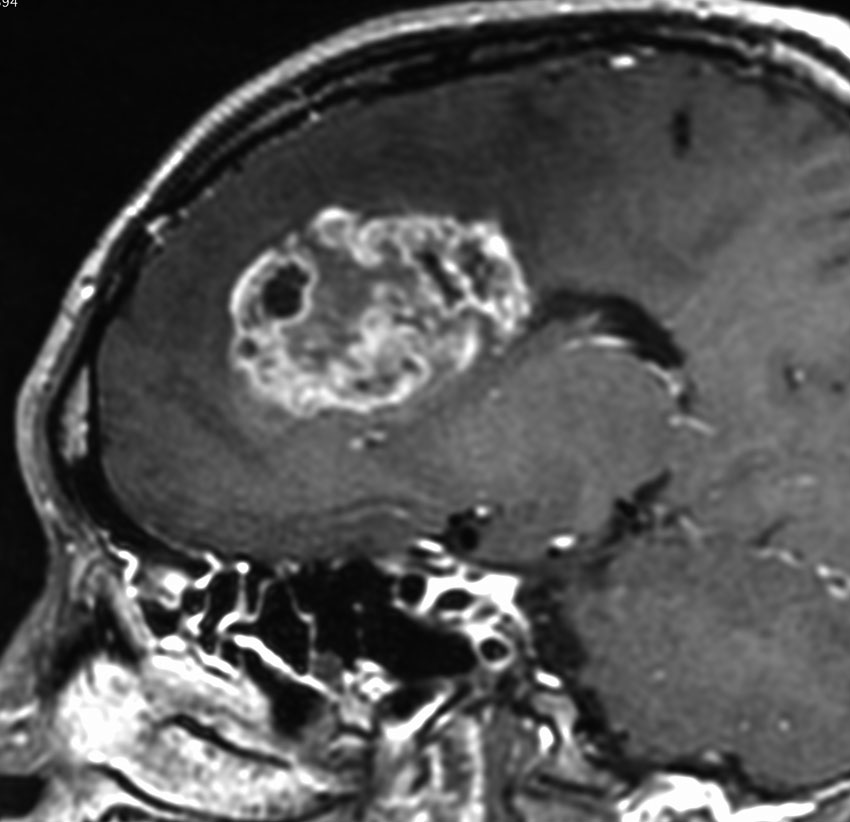

expanding, solid 固形腫瘍的なもの

壊死ではない「のう胞」を伴い,ガドリニウムで強く増強されます。グレード 4 (膠芽腫)と間違えるようなものです。しかし,のう胞はありますが中心壊死がありません。

腫瘍を大部分摘出できるので,積極的な摘出術をして,手術後には放射線化学療法を加えます。この例では,手術後の放射線治療計画の領域が狭ければ,60グレイを使用できる部位です。